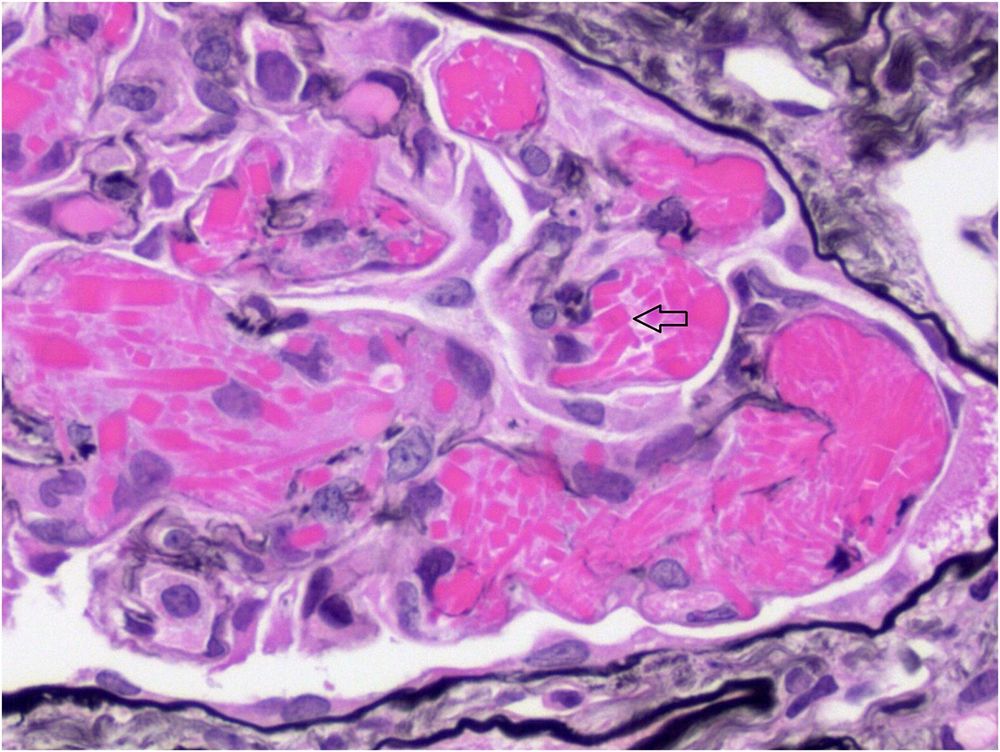

Image: Large bright eosinophilic crystals within glomerular capillaries (arrow, Jones silver stain)

Image: Large bright eosinophilic crystals within glomerular capillaries (arrow, Jones silver stain)